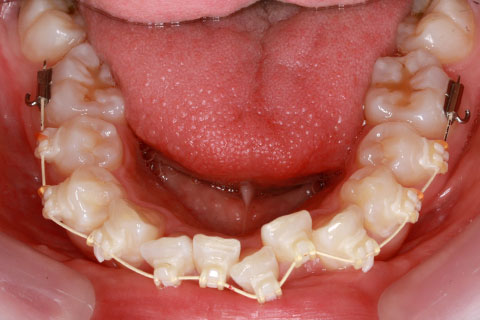

治療中(開始直後)

治療中(開始半年後)